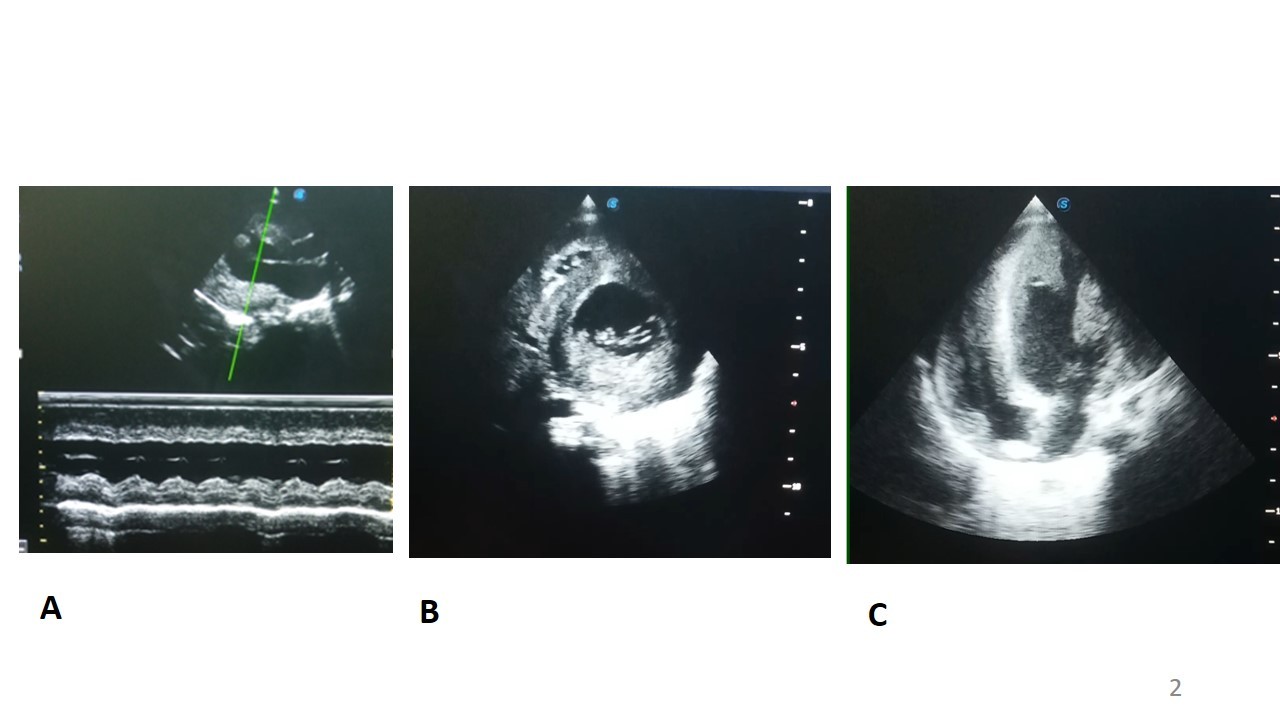

A l’échocardiographie Doppler (figure 4) on retrouvait une hypertrophie biventriculaire importante, plus marqué sur le ventricule gauche (septum interventriculaire en diastole de 10 mm, paroi postérieure en diastole de 10mm), une altération de la fonction systolique ventriculaire gauche (FEVG mesuré en Simpson bi-plan à 30%). Les cavités cardiaques gauches étaient dilatées.

L'atteinte cardiaque est fréquente et la majorité des nourrissons présentent une cardiomyopathie hypertrophique avant l'âge de 6 mois, avec une progression vers l'insuffisance cardiaque [14, 15]. L'échocardiographie est précieuse pour évaluer la structure et la fonction ventriculaires. L'hypertrophie, porte principalement sur la paroi postérieure du ventricule gauche et le septum inter ventriculaire, et peut être également biventriculaire. Elle est généralement observée chez les nourrissons au moment du diagnostic, comme ce fut le cas dans cette observation, mais peut également être identifiée avant la naissance [4, 8].

Figure 4 : Echocardiographie Doppler chez un enfant de 10 mois, porteur de maladie de la

Pompe infantile et d’un albinisme oculo-cutané.

A : mode TM en parasternal grand axe, montrant une hypertrophie concentrique du ventricule gauche avec septum intreventriculaire et paraoi postérieure mesurée en diastole à 10 mm

B : mode 2D en parasternal court axe, montrant une hypertrophie concentrique du ventricule gauche

C : mode 2D en apical 4 cavités montarnt une hypertrophie bi ventriculaire importante